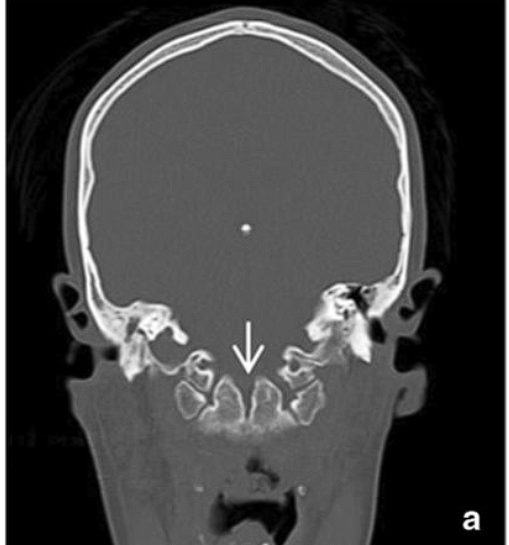

• Complete odontoid agenesis

• Syndromic

• collagenopathy or mucopolysaccharidosis such as Morquio’s disease

• may not always be due to primordial failure since a completed cartilaginous mold of the dens has been seen in situ, where ossification was found to be defective because of the abnormal connective tissue production.

• Nonsyndromic

• due to aplasia or hypoplasia of centrum primordia.

A blurry image of a person AI-generated content may be incorrect.